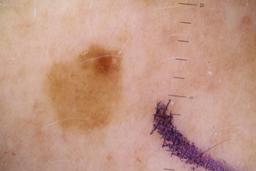

ISIC_5852089

Clinical

| anatom_site_1 | Lower extremity |

| anatom_site_2 | Foot |

| anatom_site_special | acral NOS |

| diagnosis_1 | Benign |

| image_type | dermoscopic |